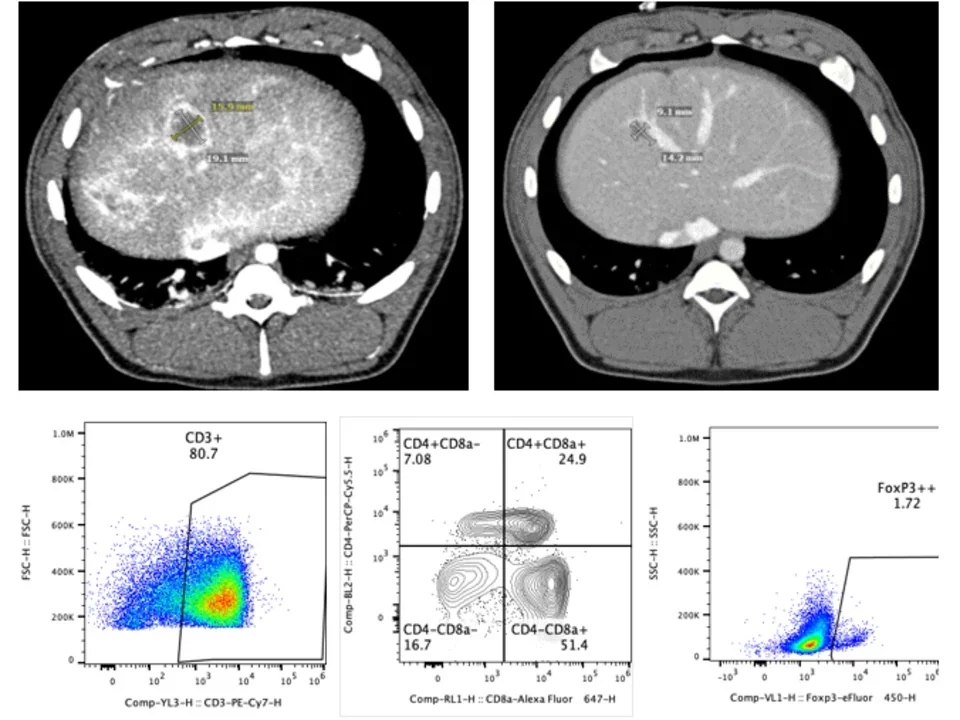

Large animal validation of minimally-invasive cancer therapy

The majority of pre-clinical oncology work has lay within the realm of small animals such as rodents. While they have a role for drug development and validation, rodents are not well equipped to validate the catheters and antennas/probes used for minimally-invasive image-guided cancer therapy. We use large animal platforms to validate the efficacy of locoregional therapy. We collaborate closely with the UCLA Translational Research and Imaging Center (TRIC), which has a dedicated research-only Siemens Prisma 3T MRI, Siemens Somatom Definition CT, and a Siemens Artis Zeego Robotic Arm system for angiography. Protocols are identical to those use clinically to facilitate translation to our own patient population. We also work with the UCLA JCCC Flow Cytometry Core to optimize immune assessment tools for large animals, including a porcine-specific CyTOF panel.

pre and post immunotherapy